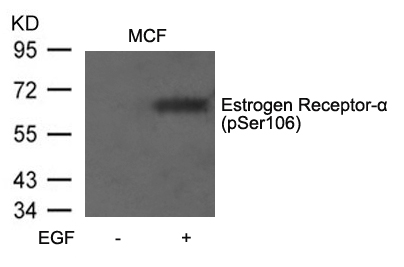

分类: 科研抗体货号: P40070别名: ER; ESR; ESR1; ESTR; ESTRA应用: WB,IHC,IF反应种属: Human,Mouse,Rat